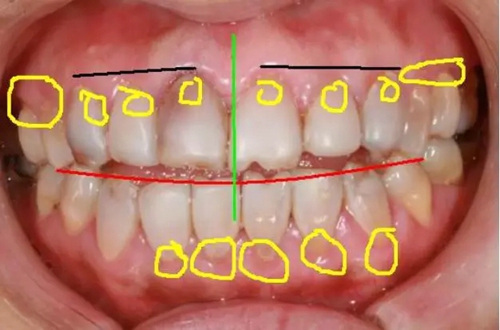

如下面圖一照片,我們在患者需要改變的地方分別做了標記,并進行先期的設(shè)計。

(圖一)

1,黑線牙齦的高度:

患者左側(cè)牙齦高度較正常,右側(cè)13的牙齦明顯低于12,右側(cè)牙齦至少要與左側(cè)接近。

2,紅線切緣:

由于患者開頜較重,縱面曲線已經(jīng)改變,所以在美學修復(fù)的同時,應(yīng)注意牙齒生理上意義。

3,綠線正中線:

正中線是起到一個均衡的意義,除上下頜盡可能對齊外,同時要保證必須與面中線一致。

4,黃線處牙齦:

患者的牙齦(牙周)已經(jīng)明顯紅腫,必須要在牙周穩(wěn)定后才能進行修復(fù)。如果是原修復(fù)體的原因,建議先拆除,去除對牙齦的刺激。如果是患者自身原因,建議治療后觀察,修復(fù)治療待定。